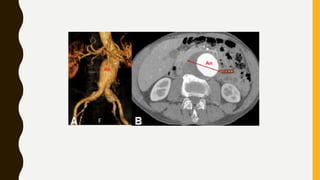

CT IN AORTIC ANEURYSM

• If a pulsatile mass is felt in abdomen, diagnosis of possible

abdominal aortic aneurysm is suspected.

• Ultrasound is modality of choice , provided aorta is not obscured by

bowel gas.

• If aneurysm is identified and information regarding extend and size

is required ( for surgical or endovascular repair planning), CT

angiography is indicated from arch to pubic symphysis in arterial

phase after iv contrast

• In case of suspected aneurysm rupture , urgent CT angiography to

performed , provided patient is hemodynamically stable